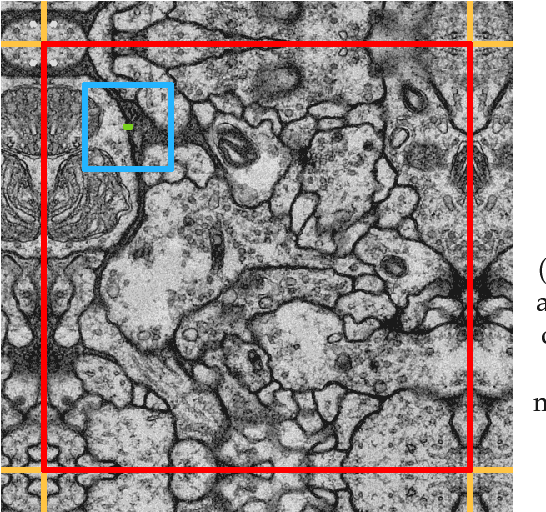

Abstract:The field of connectomics has recently produced neuron wiring diagrams from relatively large brain regions from multiple animals. Most of these neural reconstructions were computed from isotropic (e.g., FIBSEM) or near isotropic (e.g., SBEM) data. In spite of the remarkable progress on algorithms in recent years, automatic dense reconstruction from anisotropic data remains a challenge for the connectomics community. One significant hurdle in the segmentation of anisotropic data is the difficulty in generating a suitable initial over-segmentation. In this study, we present a segmentation method for anisotropic EM data that agglomerates a 3D over-segmentation computed from the 3D affinity prediction. A 3D U-net is trained to predict 3D affinities by the MALIS approach. Experiments on multiple datasets demonstrates the strength and robustness of the proposed method for anisotropic EM segmentation.

Abstract:This work presents and analyzes three convolutional neural network (CNN) models for efficient pixelwise classification of images. When using convolutional neural networks to classify single pixels in patches of a whole image, a lot of redundant computations are carried out when using sliding window networks. This set of new architectures solve this issue by either removing redundant computations or using fully convolutional architectures that inherently predict many pixels at once. The implementations of the three models are accessible through a new utility on top of the Caffe library. The utility provides support for a wide range of image input and output formats, pre-processing parameters and methods to equalize the label histogram during training. The Caffe library has been extended by new layers and a new backend for availability on a wider range of hardware such as CPUs and GPUs through OpenCL. On AMD GPUs, speedups of $54\times$ (SK-Net), $437\times$ (U-Net) and $320\times$ (USK-Net) have been observed, taking the SK equivalent SW (sliding window) network as the baseline. The label throughput is up to one megapixel per second. The analyzed neural networks have distinctive characteristics that apply during training or processing, and not every data set is suitable to every architecture. The quality of the predictions is assessed on two neural tissue data sets, of which one is the ISBI 2012 challenge data set. Two different loss functions, Malis loss and Softmax loss, were used during training. The whole pipeline, consisting of models, interface and modified Caffe library, is available as Open Source software under the working title Project Greentea.